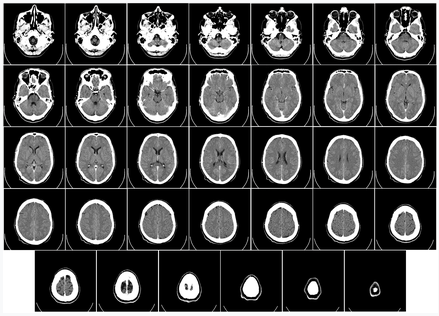

아래 그림처럼 뇌 CT의 스캔파일 생성시 그 촬영순서와 관련해서 질문드립니다.

머리 꼭대기 부분(그림기준에서는 최하단 우측부분)의 단층촬영 스캔파일 생성 후, 점차 턱 쪽(그림기준에서는 최상단 좌측부분)으로 조금씩 이동하면, 단층촬영 스캔파일을 생성 및 저장하는 걸로 느껴지는 데 맞나요?

설마 턱부분 부터 촬영해서, 머리꼭대기에서 촬영을 종료하는 것은 아니겠죠?

보통 촬영 전 엑스레이를 한 장 찍어서 어디서부터 어디까지 CT 스캔을 할 것인지 영역을 정합니다. 그리고 말씀하신 것처럼 위에서 아래로 스캔하는 편입니다.

보통은 머리끝에서부타 아래로 내려오면서 촬영이 이루어지게 됩니다 ///////////